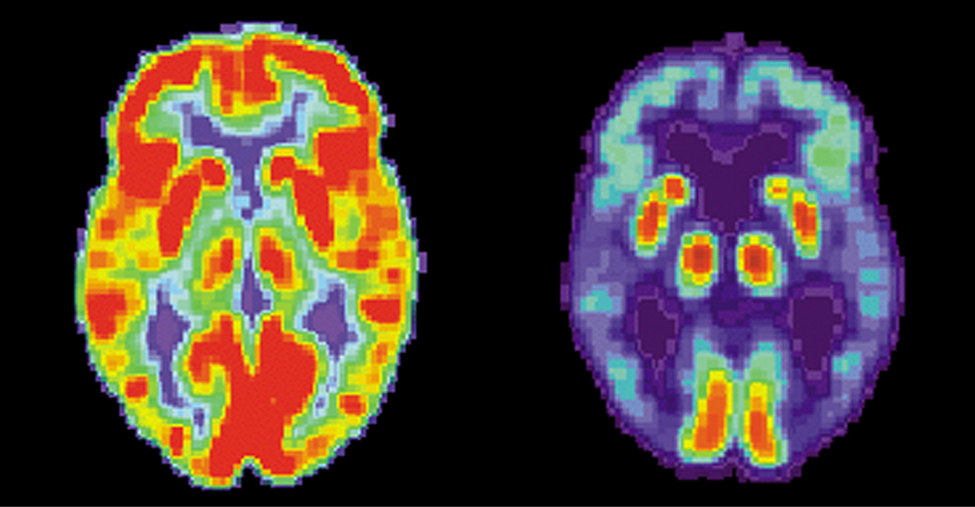

Two images of brains are shown. The one on the left has many red and orange areas and some blue areas. The one on the right is mostly blue with very small areas in red and yellow.

Figure 10.27 These brain images are produced using a radiopharmaceutical. The colors indicate relative metabolic or biochemical activity (red indicates high activity and blue indicates low activity). The figure on the left shows the normal brain of an individual and the figure on the right shows the brain of someone diagnosed with Alzheimer’s disease. The brain image of the normal brain indicates much greater metabolic activity (a larger fraction of red and orange areas). (credit: modification of works by National Institutes of Health)

PET scans are especially useful to examine the brain’s anatomy and function. For example, PET scans can be used to monitor the brain’s use of oxygen and water, identify regions of decreased metabolism (linked to Alzheimer’s disease), and locate different parts of the brain responsible for sight, speech, and fine motor activity